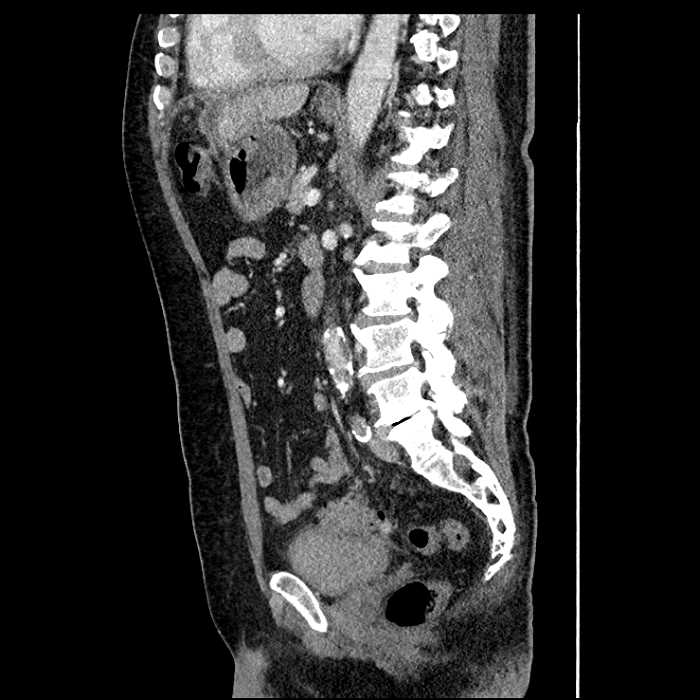

• Mild mural thickening of a segment of the sigmoid colon with adjacent fat stranding and a 1.5 cm fluid and gas collection along the tip of an inflamed diverticulum

• Loss of the normal fat plane between this collection and adjacent loops of small bowel, which demonstrate mural thickening

• No bowel obstruction

Acute sigmoid diverticulitis complicated by a small contained perforation and a large abscess in the right hepatic lobe. Additional small subcapsular abscesses along the anterior margin of the left hepatic lobe.

Additionally, loss of the normal fat plane between the peridiverticular collection and adjacent thickened loops of small bowel raises the potential for an enterocolonic fistula.

Hepatic abscess showing the double target sign with low density internally surrounded by a thin inner enhancing rim (red arrow) and ill-defined outer low density rim (yellow arrow). Blue arrow indicates an internal septation. Red arrows: additional smaller subcapsular abscesses. Red arrow: focal contained perforation associated with diverticulitis.